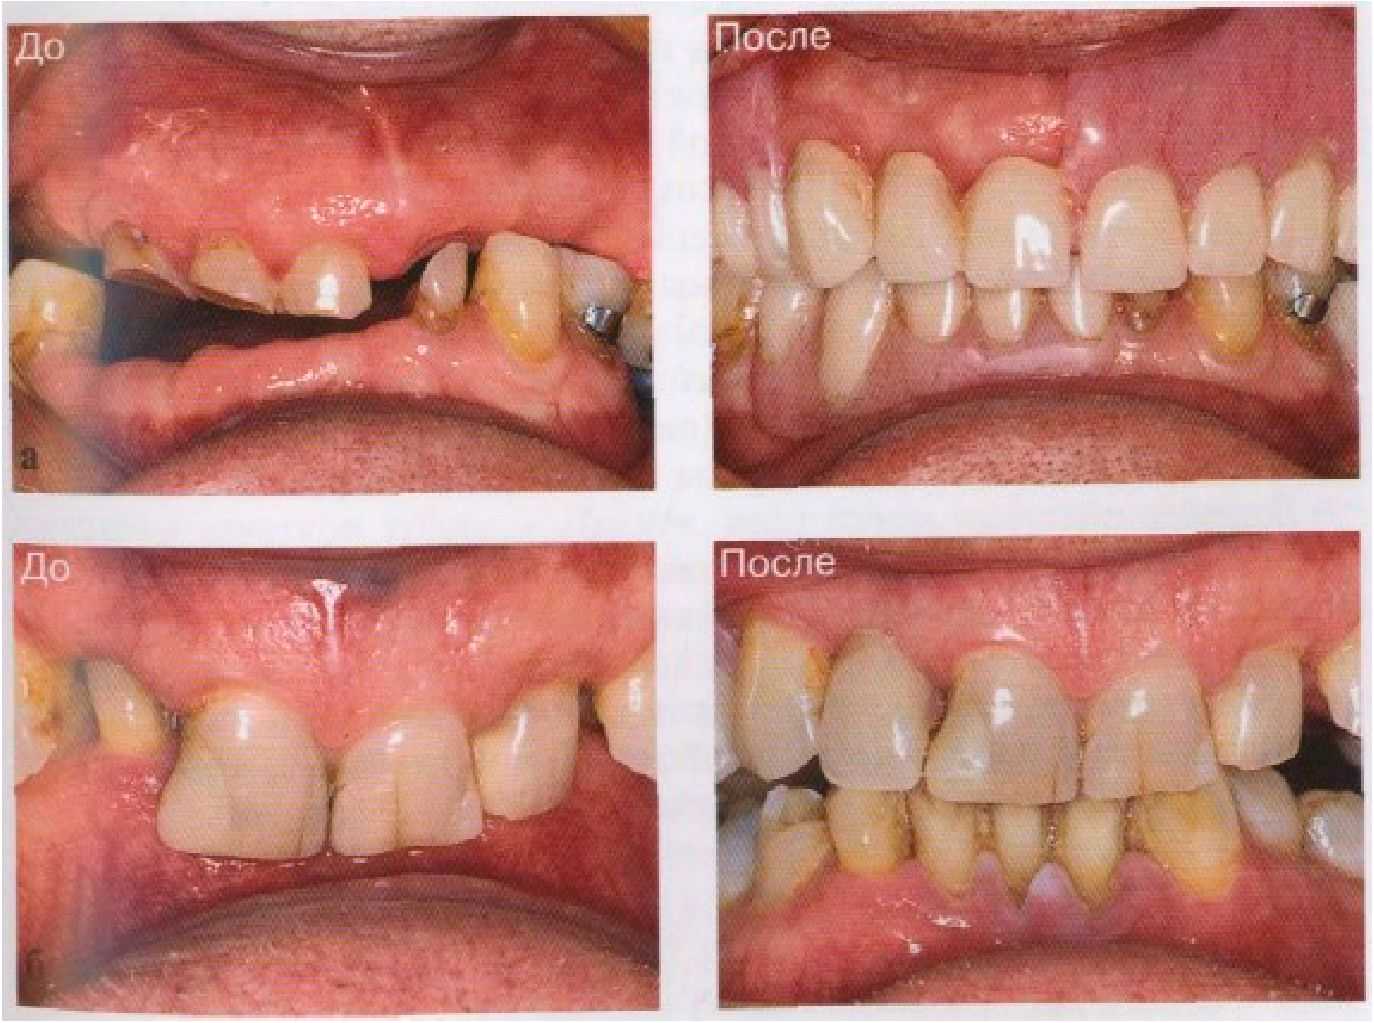

Создание временных частичных съемных протезов часто показано при повышенной стираемости зубов и связанной с этим потере окклюзионной высоты лица (рис. 7-5). Эти съемные протезы используются с

Рис. 7-5. (а б) Примеры применения временных частичных съемных протезов в качестве промежуточного средства восстановления приемлемого внешнего вида и увеличения высоты лица.

целью замещения утраченных зубов и сохранения стабильной окклюзии с учетом приемлемой окклюзионной высоты лица до и во время создания постоянных искусственных коронок, несъемных и съемных протезов.